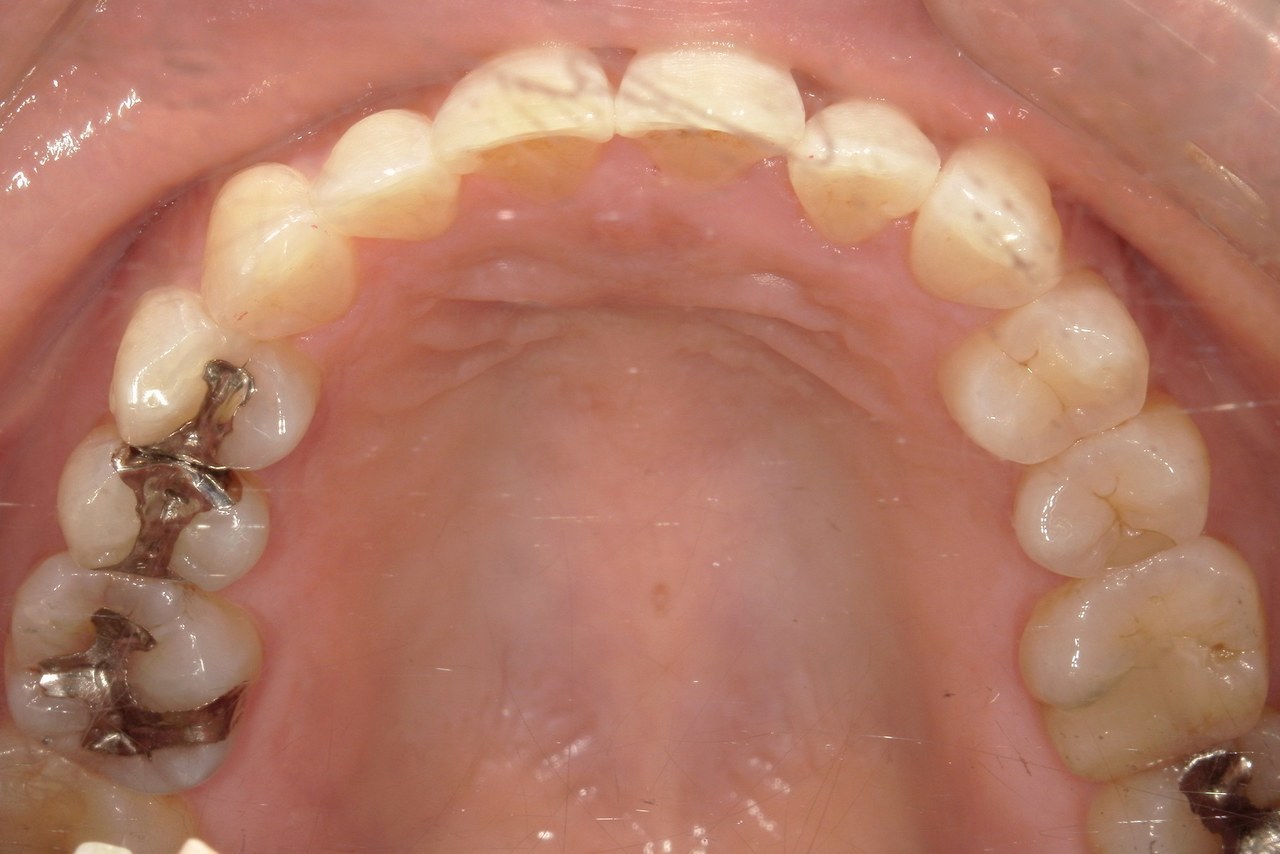

Before

浜松市中央区・自動車学校前駅のインビザラインの症例

Y.S. 30代男性

全体的にガタガタしているのが気になるという主訴だったため、上下左右第一小臼歯を抜歯し、叢生を並べました。

治療の期間:R3. 9/1〜R5. 10/31

治療の価格:88万円